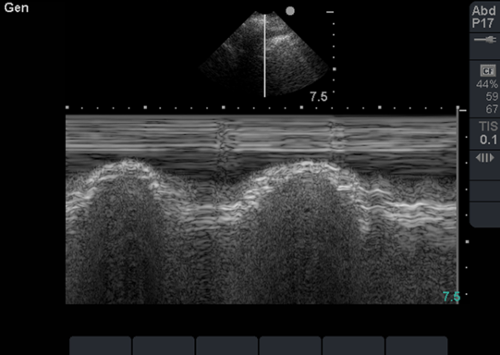

Chest radiograph is pending. In the interim, bedside lung sonography is performed, and the following finding is present on examination of the right lung.

Question 1: The image is consistent with the presence of which of the following:

Question 2: The image can be best described as:

A. Bat sign

B. Sinusoid sign

C. Curtain sign

D. Seashore sign